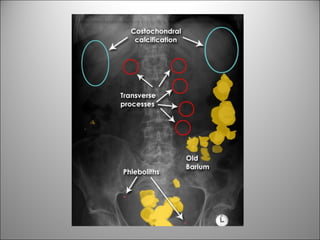

HUESOS

CALCIFICACIONES Y ARTEFACTOS